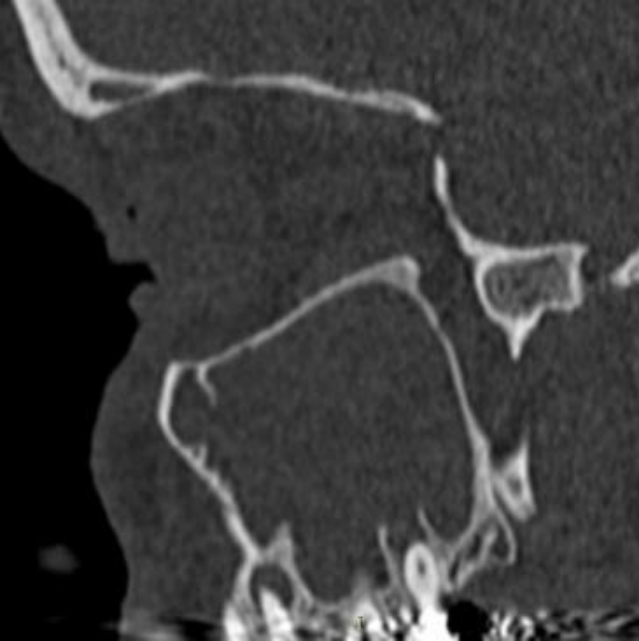

Imagem de tomografia computadorizada em janelamento ósseo, no plano sagital, demonstando Obliteração total do seio maxilar direito, associado comunicação oroantral, caracterizada por descontinuidade da da membrana de Schneiderian, com da perfuração do assoalho do seio.